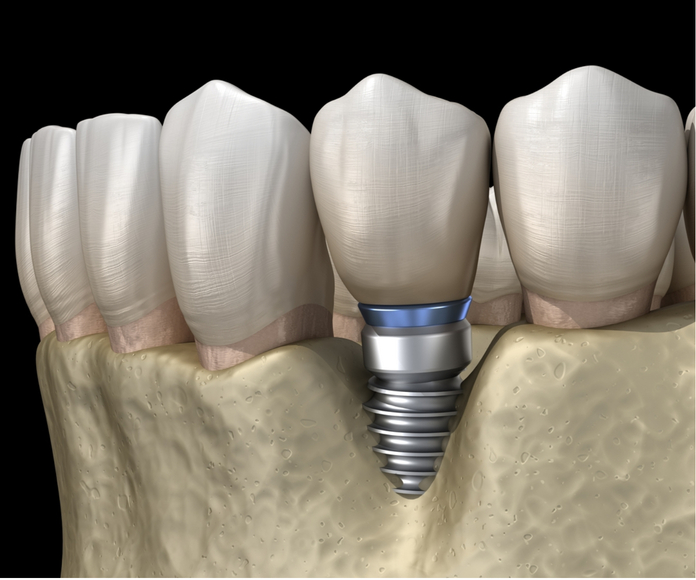

nướu có thể bị tụt dần (như hình bên dưới) và

trụ implant gắn trong nướu có thể bị lộ ra bên ngoài.

Trụ Implant lộ ra bên ngoài.

Như hình trên trụ implant có hình

dạng giống như một chiếc ốc vít.

Nếu xoắn ốc này lộ ra bên ngoài,

thức ăn có thể mắc vào vùng rỗng vi khuẩn có thể xâm nhập.

Một khi điều đó xảy ra, không dễ để làm sạch nó chỉ bằng cách đánh răng.